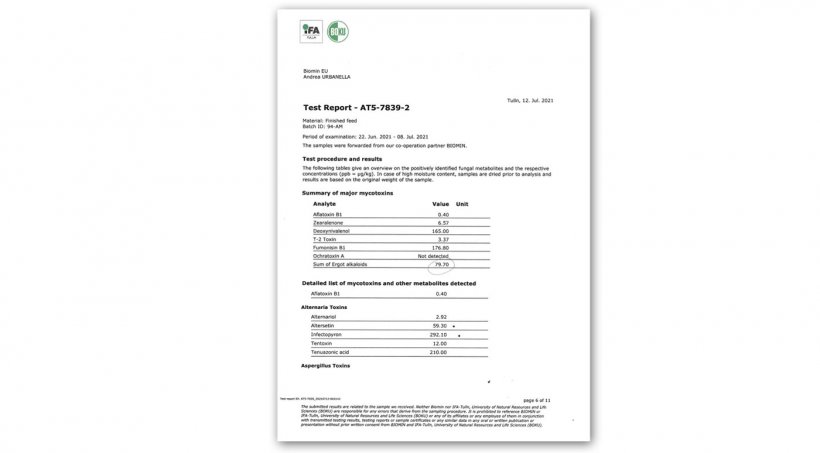

3- Des contrôles de l'aliment ont été effectués qui n'ont pas révélé d'écarts significatifs dans les paramètres nutritionnels. La surveillance des mycotoxines a trouvé des valeurs très faibles, seuls les niveaux d'alcaloïdes de l'ergot de seigle ont montré des niveaux d'importance possible. Des niveaux étrangement élevés de phytoestrogènes ont été observés, mais l'origine et la signification doivent encore être explorées.

Figure 10. Test mycotoxines